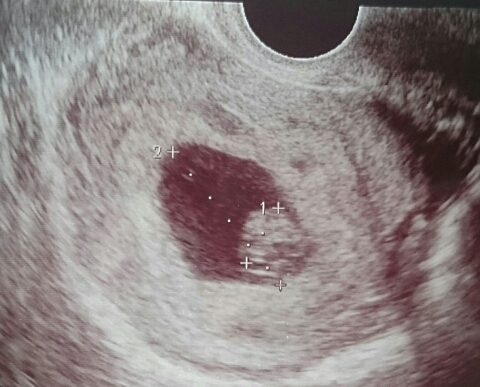

JUGEMテーマ:妊娠中のできごと 7週目にして小さい胎嚢しか確認できず、毎日不安のなかつわりの症状が出始めて赤ちゃんが成長しているんだと信じて毎日子宝授かりのお守りを枕元に置いた。神棚の前でお願いもして、とにかく念じていた(笑) 毎日基礎体温をはかりつづけて、下がっていないことを確認してホッとする朝の繰り返し。 そして二週間の検診の日、夫と病院へ。 赤ちゃんが成長していることがわかりました。うれしくてまた涙がうるっとして先...